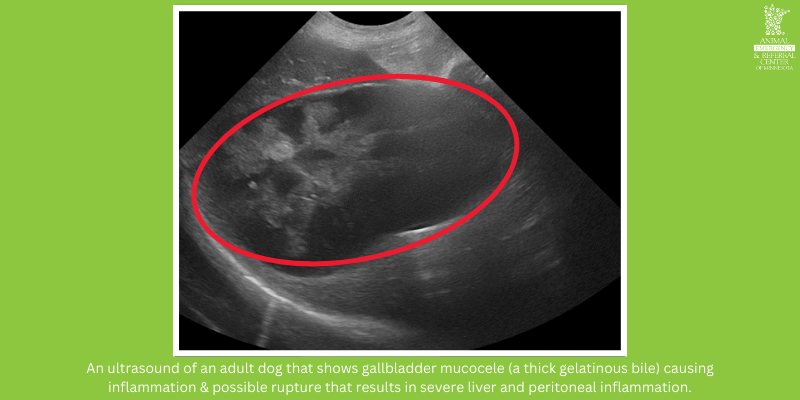

An ultrasound of an adult dog that shows gallbladder mucocele (a thick gelatinous bile) causing inflammation & possible rupture that results in severe liver and peritoneal inflammation. Ultrasound provided by Animal Emergency & Referral Center of Minnesota.

2. Liver Inflammation

When a dog or cat has abnormal liver values, an ultrasound is needed to localize the disease and to determine if it’s acute inflammation, chronic inflammation, or cancer.

What the Radiologist Sees:

• When the diagnosis is inflammation and infectious diseases:

• Mixed/hazy appearance

• Enlargement and rounding, thickening of the gallbladder, bile ducts, and nodules (a growth of abnormal tissue).